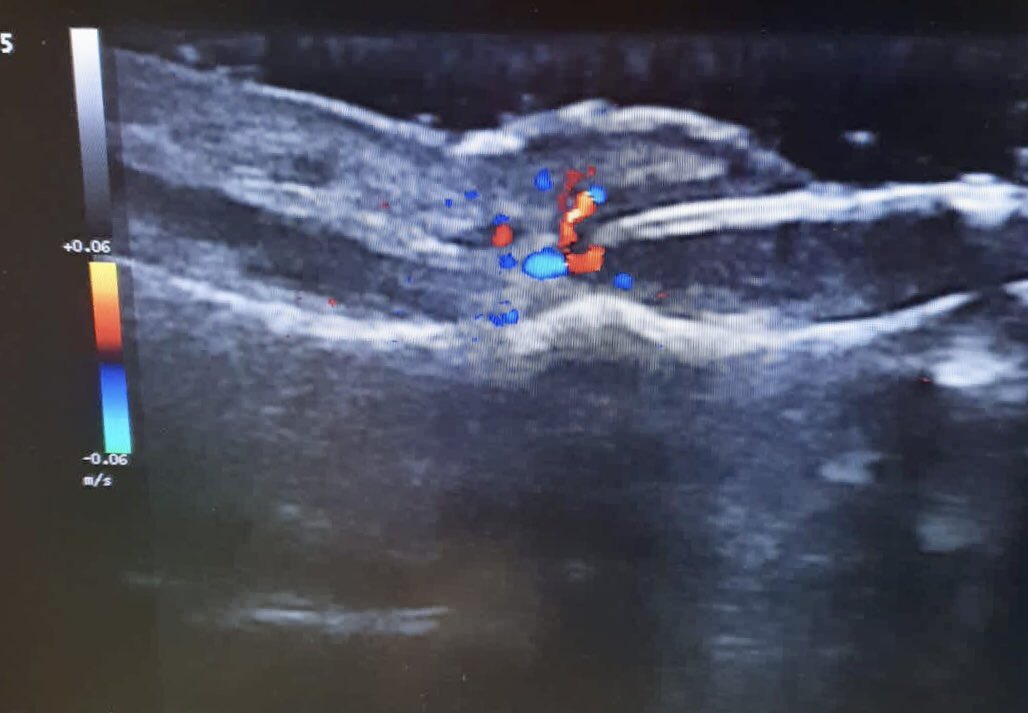

La retroniquia puede producir un dolor muy intenso por la inflamación del pliegue proximal ungueal y la sobreinfección. Aquí el hallux valgus (juanete) del paciente es el factor desencadenante. La solución es sencilla:laminectomía total con alivio rápido del dolor La eco ayuda!

La retroniquia puede producir un dolor muy intenso por la inflamación del pliegue proximal ungueal y la sobreinfección. Aquí el hallux valgus (juanete) del paciente es el factor desencadenante.

La solución es sencilla:laminectomía total con alivio rápido del dolor

La eco ayuda!